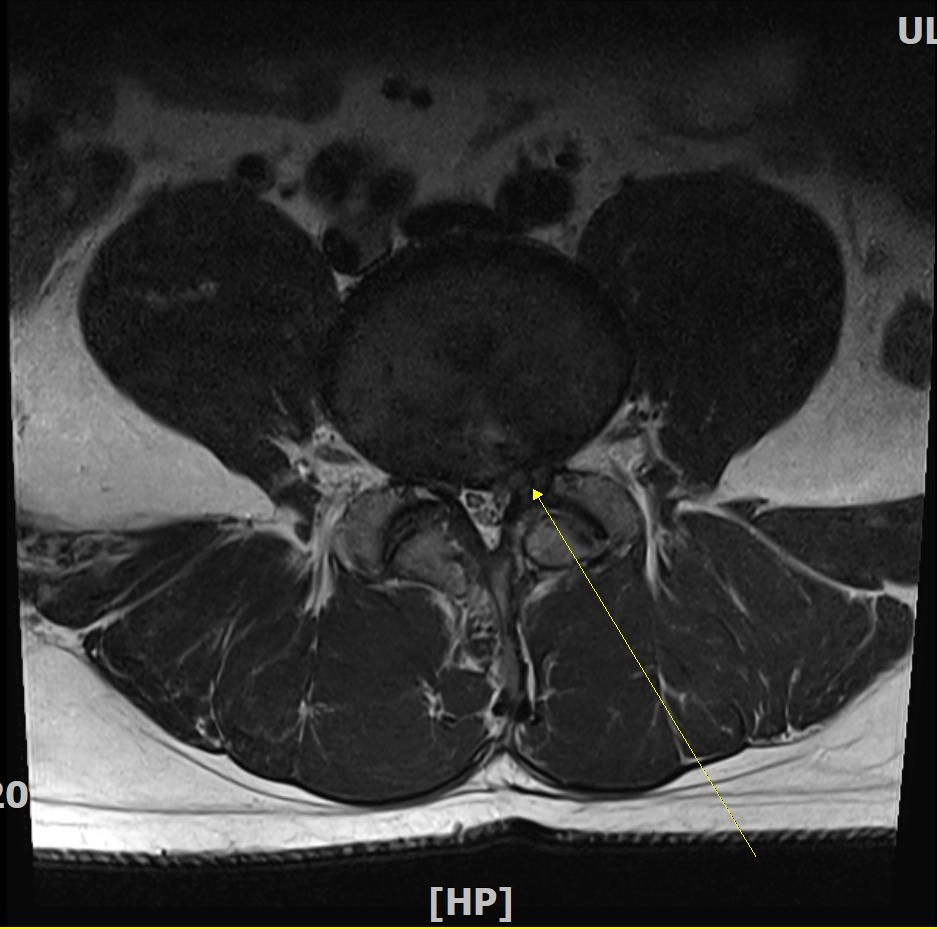

판독부탁드립니다. L4-5번 후궁절제술 및 디스크 제거술 2004년도에 실시하였으며 금번 mri상 추간판탈출증소견 받았습니다. 재발인지 궁금합니다

20년전 수술로 인하여 신경손상이 의심되는데 현재 하지방사통 및 종아리 발가락 등 오래 걷지못하고 일상생활에 지장이 옵니다. 감사합니다

• 2번 째 사진

근전도 검사 결과 요추 5번 신경뿌리병증이 보인다는 내용입니다. 재발이라고 단언할 수는 없으나 과거 수술한 위치와 동일한 것으로 추정됩니다. 잘 치료하여 회복되시길 바랍니다.